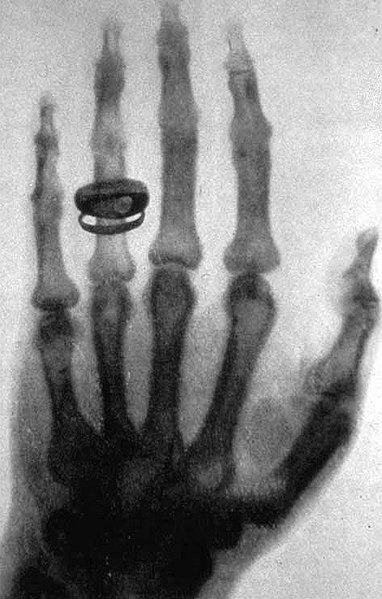

On the other hand, what I find interesting is Ord’s implication that cameras and even compasses extend our perception into the “hidden world of peculiar and unknown energy,” possibly wherein spirits dwell. (Crisis apparitions, he posits, grant a peek into that world.) When he refers to cameras, by the way, I doubt he’s suggesting spirit photography. It was too controversial, too fraught with fakery, and not exactly the “[r]ecent science” Ord mentions because it had been around for over three decades when the essay appeared. Instead, he probably means X-rays, which had been detected only a couple of years earlier.